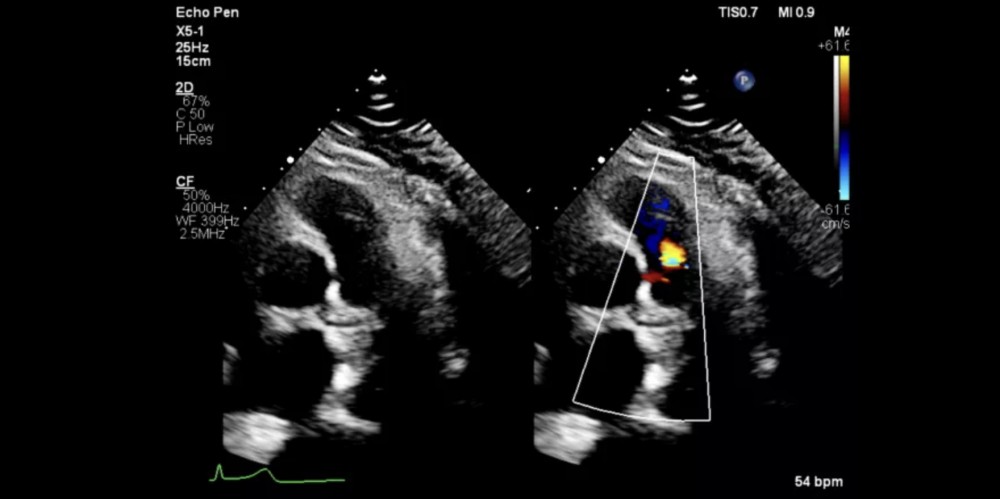

Təkmilləşdirilmiş Görüntüləmə Modalları

Live xPlane imaging, iRotate, Live 3D (3D TEE daxil olmaqla)

X5-1: xMatrix / yetkin eko (2D, Live xPlane)

S5-1X5-1 probları isə bütün xəstə növlərində, hətta texniki baxımdan çətin xəstələrdə belə, əla görüntü keyfiyyəti təmin edir.